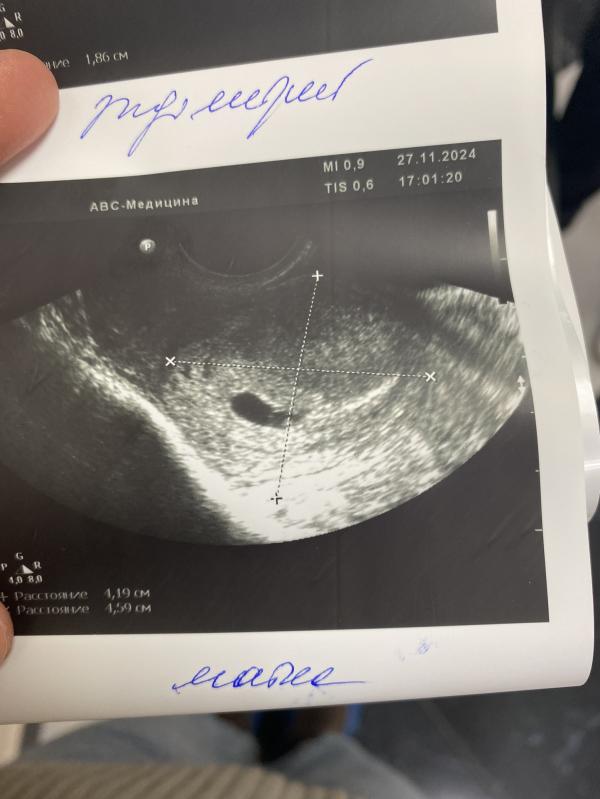

Девочки ! Кто переживал , я только что с Узи сердечко ♥️ бьется и мы развиваемся как надо

Спасибо кто переживал за нас💗